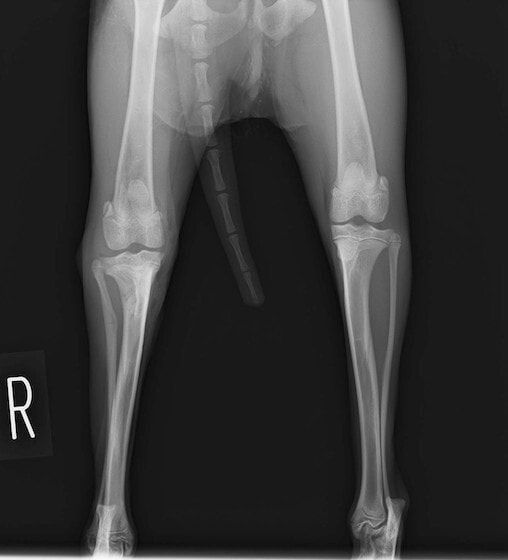

脛骨骨折 : 症例1 | 症例2 | 症例3 | 症例4 | 症例5

Advanced Locking plate system と Locking compression plate system

当院ではAdvanced Locking plate system(ALPS)と、Locking compression plate system(LCPS)という骨接合法で骨折症例の治療を行っています。

Advanced Locking Plate System

従来型のプレートのように広い面積で骨と接するプレートを用いて固定を行った場合、プレート下の骨はプレートとの接触面において血行が絶たれ壊死し、それがリモデリングされると骨密度が低下する。この骨密度の低下防ぐために、骨折部局所への血行を温存することの重要性が近年改めて認識されるようになってきている。Advaed Locking Plate System (ALPS)は従来型のプレートシステムの欠点を改良し、より使いやすく、より骨への血行を阻害しないようにというコンセプトで作られた。